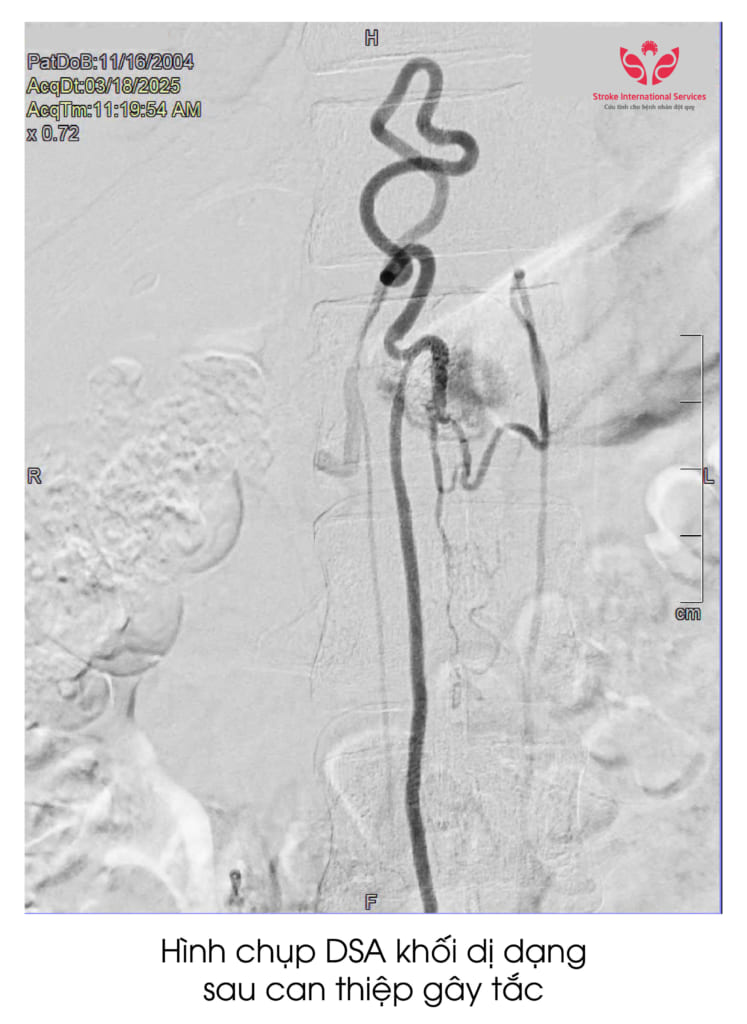

Rất may mắn bệnh nhân đã được tiến hành điều trị kịp thời. Ê kíp bác sĩ đã tiến hành hội chẩn và có chỉ định điều trị can thiệp gây tắc mạch máu. Sau khi gây tắc chỗ thông động tĩnh mạch tủy đã được chữa khỏi hoàn toàn. Túi phình có kích thước rất lớn nên cần phải mổ cắt bỏ hoàn toàn vùng dị dạng. Như vậy mới có cơ hội phục hồi cho bệnh nhân.